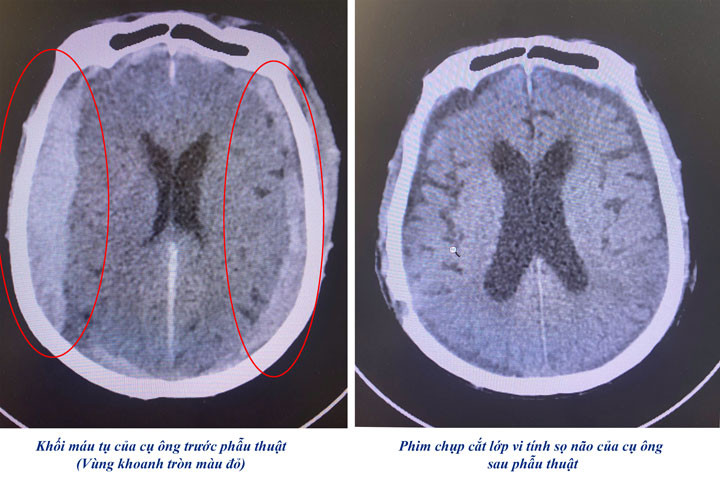

Ngay khi tiếp nhận, các bác sĩ tiến hành thăm khám và làm các xét nghiệm chẩn đoán. Kết quả chụp cắt lớp vi tính sọ não cho thấy hình ảnh chảy máu dưới màng cứng 2 bên số lượng nhiều, chảy máu ở lều tiểu não.

Người bệnh được chẩn đoán tụ máu dưới màng cứng 2 bên và được chỉ định phẫu thuật cấp cứu lấy khối máu tụ, cầm máu, giải ép não.

Sau hơn 3 giờ phẫu thuật, khối máu tụ được lấy bỏ, cầm máu, giải phóng áp lực chèn ép ở hai bên bán cầu đại não. Bằng kiến thức chuyên sâu và kinh nghiệm xử trí, ca phẫu thuật đã được thực hiện thành công. Hiện sức khỏe người bệnh ổn định và đã ra viện.